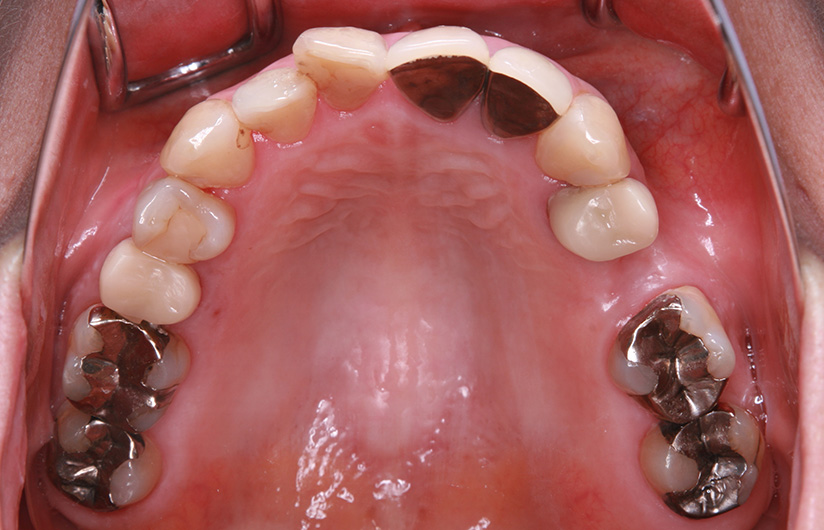

症例紹介

1歯義歯治療の例

術前・術後の比較

| 患者属性 | 50代 女性 |

|---|---|

| 主訴 | 左上の歯ぐきが痛む |

| 診断 | 左上5 歯根破折 |

| 補綴装置 | ノンクラスプデンチャー |

| 治療期間 | 約2ヵ月 |

| 通院回数 | 2回 |

| 治療費 | ノンクラスプデンチャー治療(1歯):110,000円(税込) |

| 治療内容 | 左上5の抜歯術を行い、治癒期間(約1か月)を得て、2回の義歯治療で義歯を作成しています。 |

| リスクと副作用 | 歯がないところの横の歯(隣在歯)に義歯をひっかけるため、その支えとなる歯には、ブリッジ治療と同様の影響があります。 |